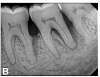

(11.) Preoperative periapical radiograph taken on November 11, 2015.

Figure 11

(12.) Follow-up radiographs taken of teeth Nos. 17, 18, and 19 on September 4, 2020 after almost 5 years post-initial scaling and root planing and alternating supportive periodontal maintenance therapy only.

Figure 12

(13.) Follow-up radiographs taken of teeth Nos. 17, 18, and 19 on September 4, 2020 after almost 5 years post-initial scaling and root planing and alternating supportive periodontal maintenance therapy only.

Figure 13

A 63-year-old male patient with a medical history of asthma, hay fever, sinusitis, and arthritis was referred for periodontal therapy in November 2015. He reported taking multivitamins, fish oil, and naproxen sodium occasionally for pain. The patient did not report experiencing any dental discomfort. The clinical findings, radiographic interpretations, diagnosis, and preoperative prognosis for teeth Nos. 17 through 19 are summarized in Figure 6 and Table 1. The patient was informed that teeth Nos. 17 and 18 should be extracted and that tooth No. 19 would need regenerative therapy. A treatment plan was devised for phase I and phase III periodontal therapy, and the patient consented to the proposed treatment verbally and in writing.

The patient's periodontal disease improved with initial nonsurgical periodontal therapy that involved scaling and root planing. This initial treatment was followed by only SPT every 3 months. Despite treatment, residual deep periodontal probing depths remained, so a decision was made to maximize improvements with nonsurgical therapy and to reassess as needed to determine whether surgical intervention was appropriate. After almost 5 years of SPT and good patient compliance with plaque control and supportive care, the periodontium was stable. Because of the resulting bone formation and improvements in clinical attachment levels (Figure 7 through Figure 13), it was determined that periodontal surgical intervention was not necessary.

Although rare, the radiographic evidence in the current case indicated that nonsurgical therapy effectively halted the destructive effects of severe chronic periodontitis and led to bone regeneration, thereby eliminating the need for surgery. The current case also showed that nonsurgical periodontal therapy may lead to desirable outcomes for patients with severe chronic periodontal disease if the patient is compliant with plaque control, supportive periodontal therapy is provided, etiological and risk factors are eliminated, and the body is given adequate time to heal.11 An additional factor that may have influenced the positive outcome of the current case was the patient's favorable health status.